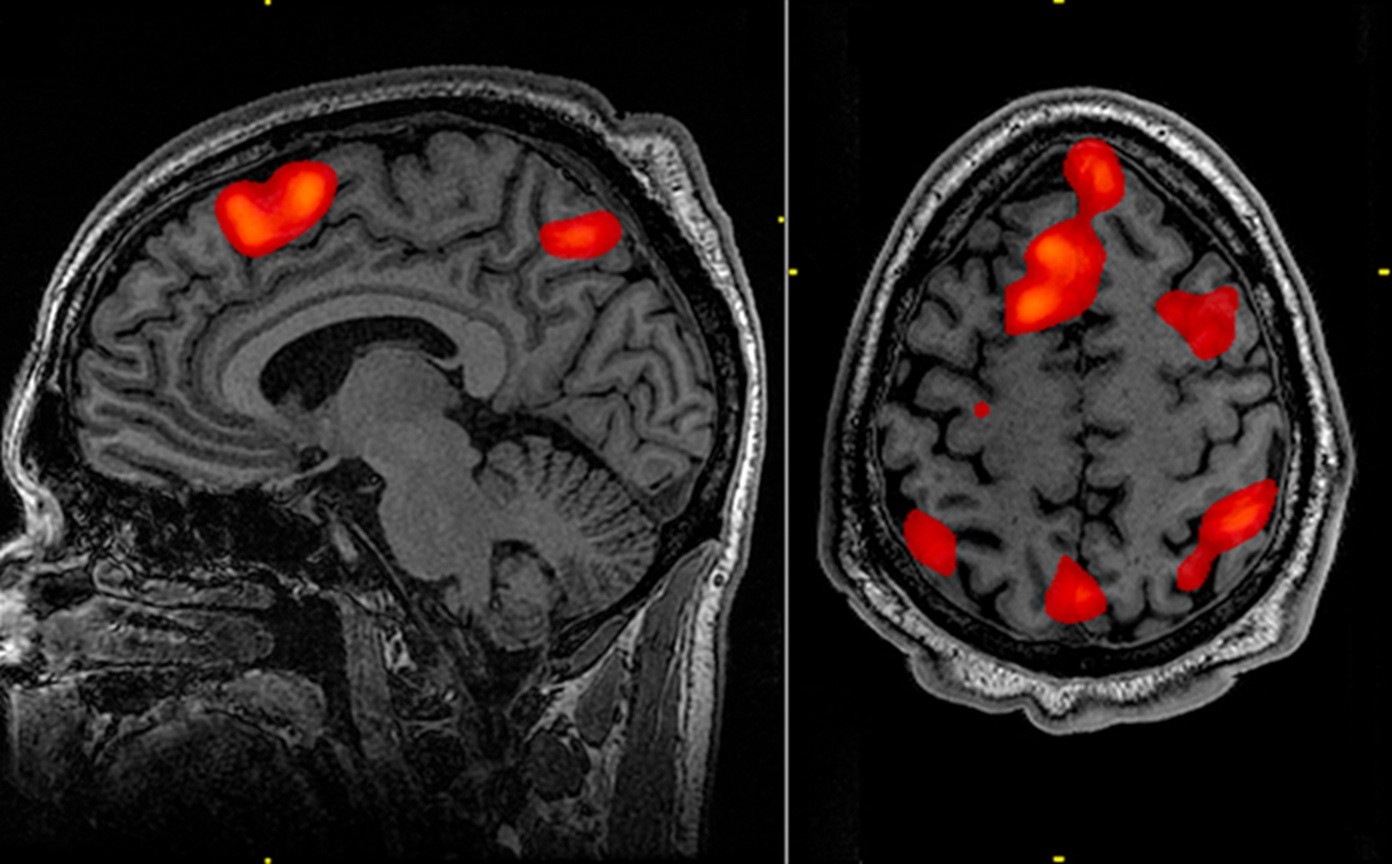

Ele é introduzido profundamente no cérebro, usando imagens de ressonância magnética para orientar um microcateter em duas regiões do cérebro, o núcleo caudado e o putâmen. A neurocirurgia leva entre 12 e 18 horas.